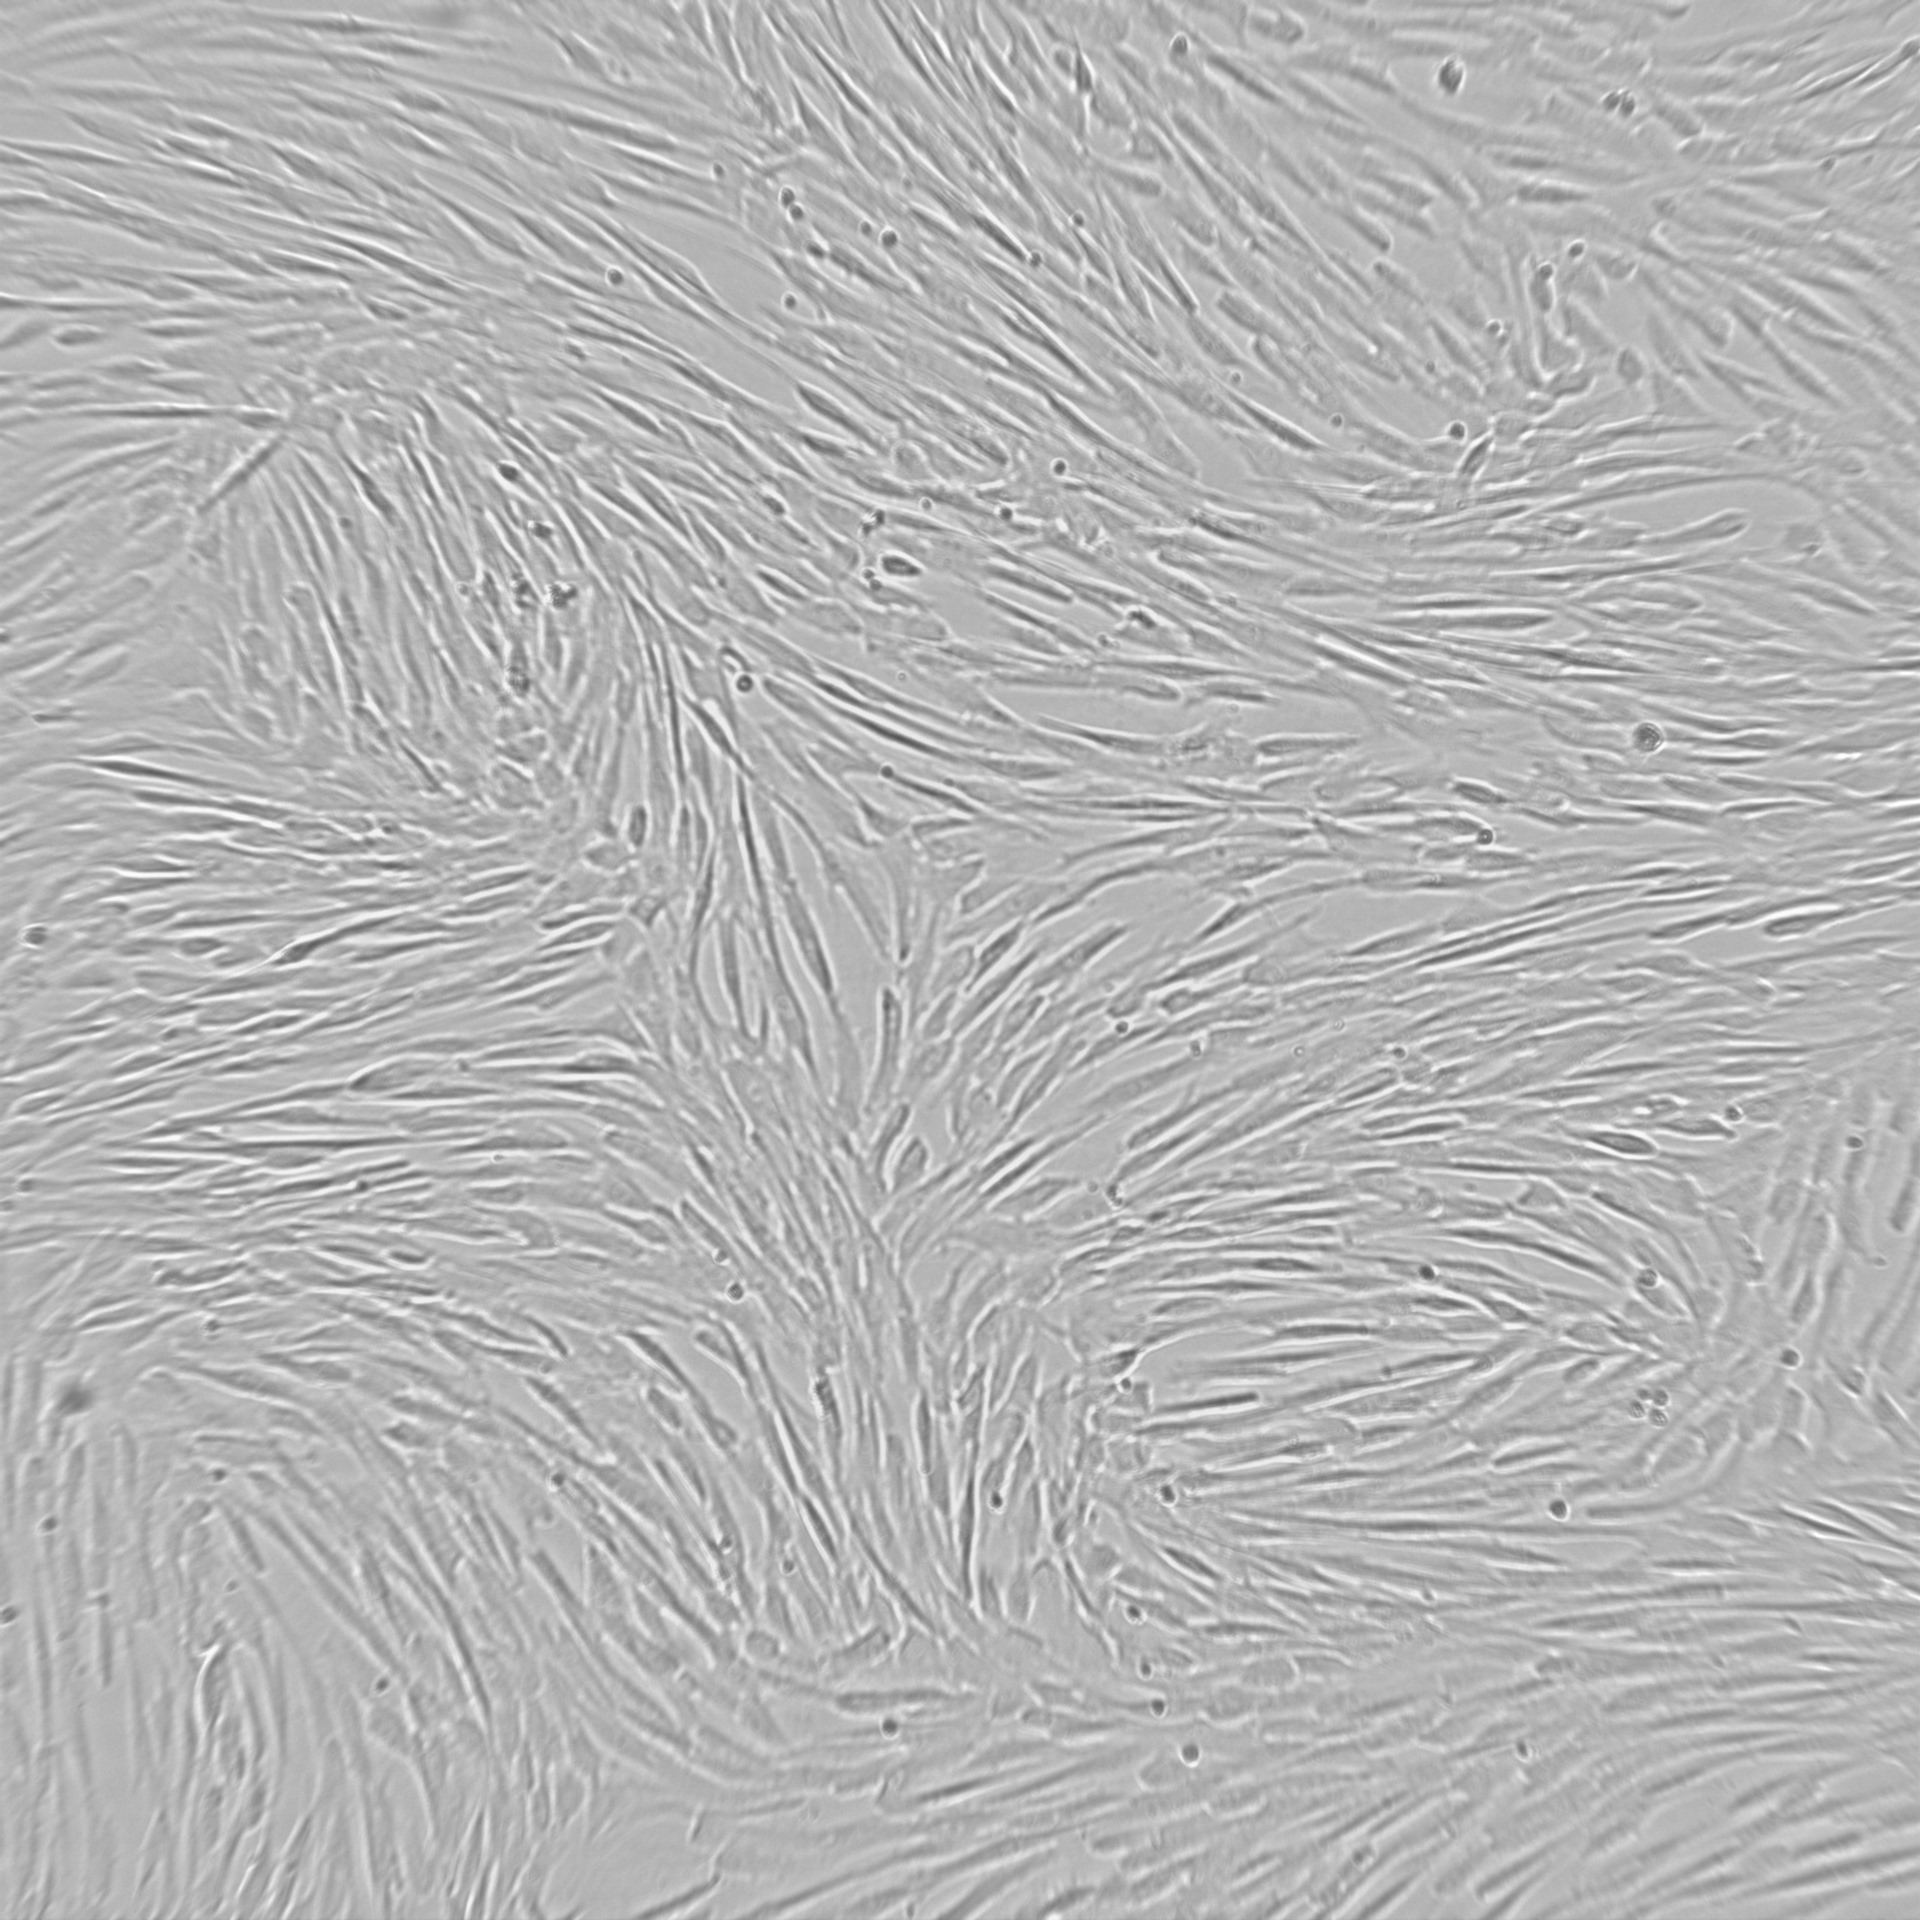

Mesenchymal stromal cells isolated from human umbilical cord and seen under the microscope

Mesenchymal stromal cells (MSCs) are specific cells found in human umbilical cord that is usually discarded as medical waste. The cord tissues for this project were obtained from the 'Biobank Antwerpen' in Belgium, provided by the donors upon written informed consent. These cells can be isolated in the laboratory and secrete so called extracellular vesicles (MSC-EVs). The latter are very small, nano size biological particles containing many different types of therapeutically active molecules. During the last years, accumulating evidence show that MSC-EVs can stop brain inflammation and, on the top of that, start regeneration of already occurred brain damage in animal models. However, most of these studies produced MSC-EVs not according to the strict Good Manufacturing Practice (GMP) requirements applicable for medicinal drugs which is a must to be used on humans.